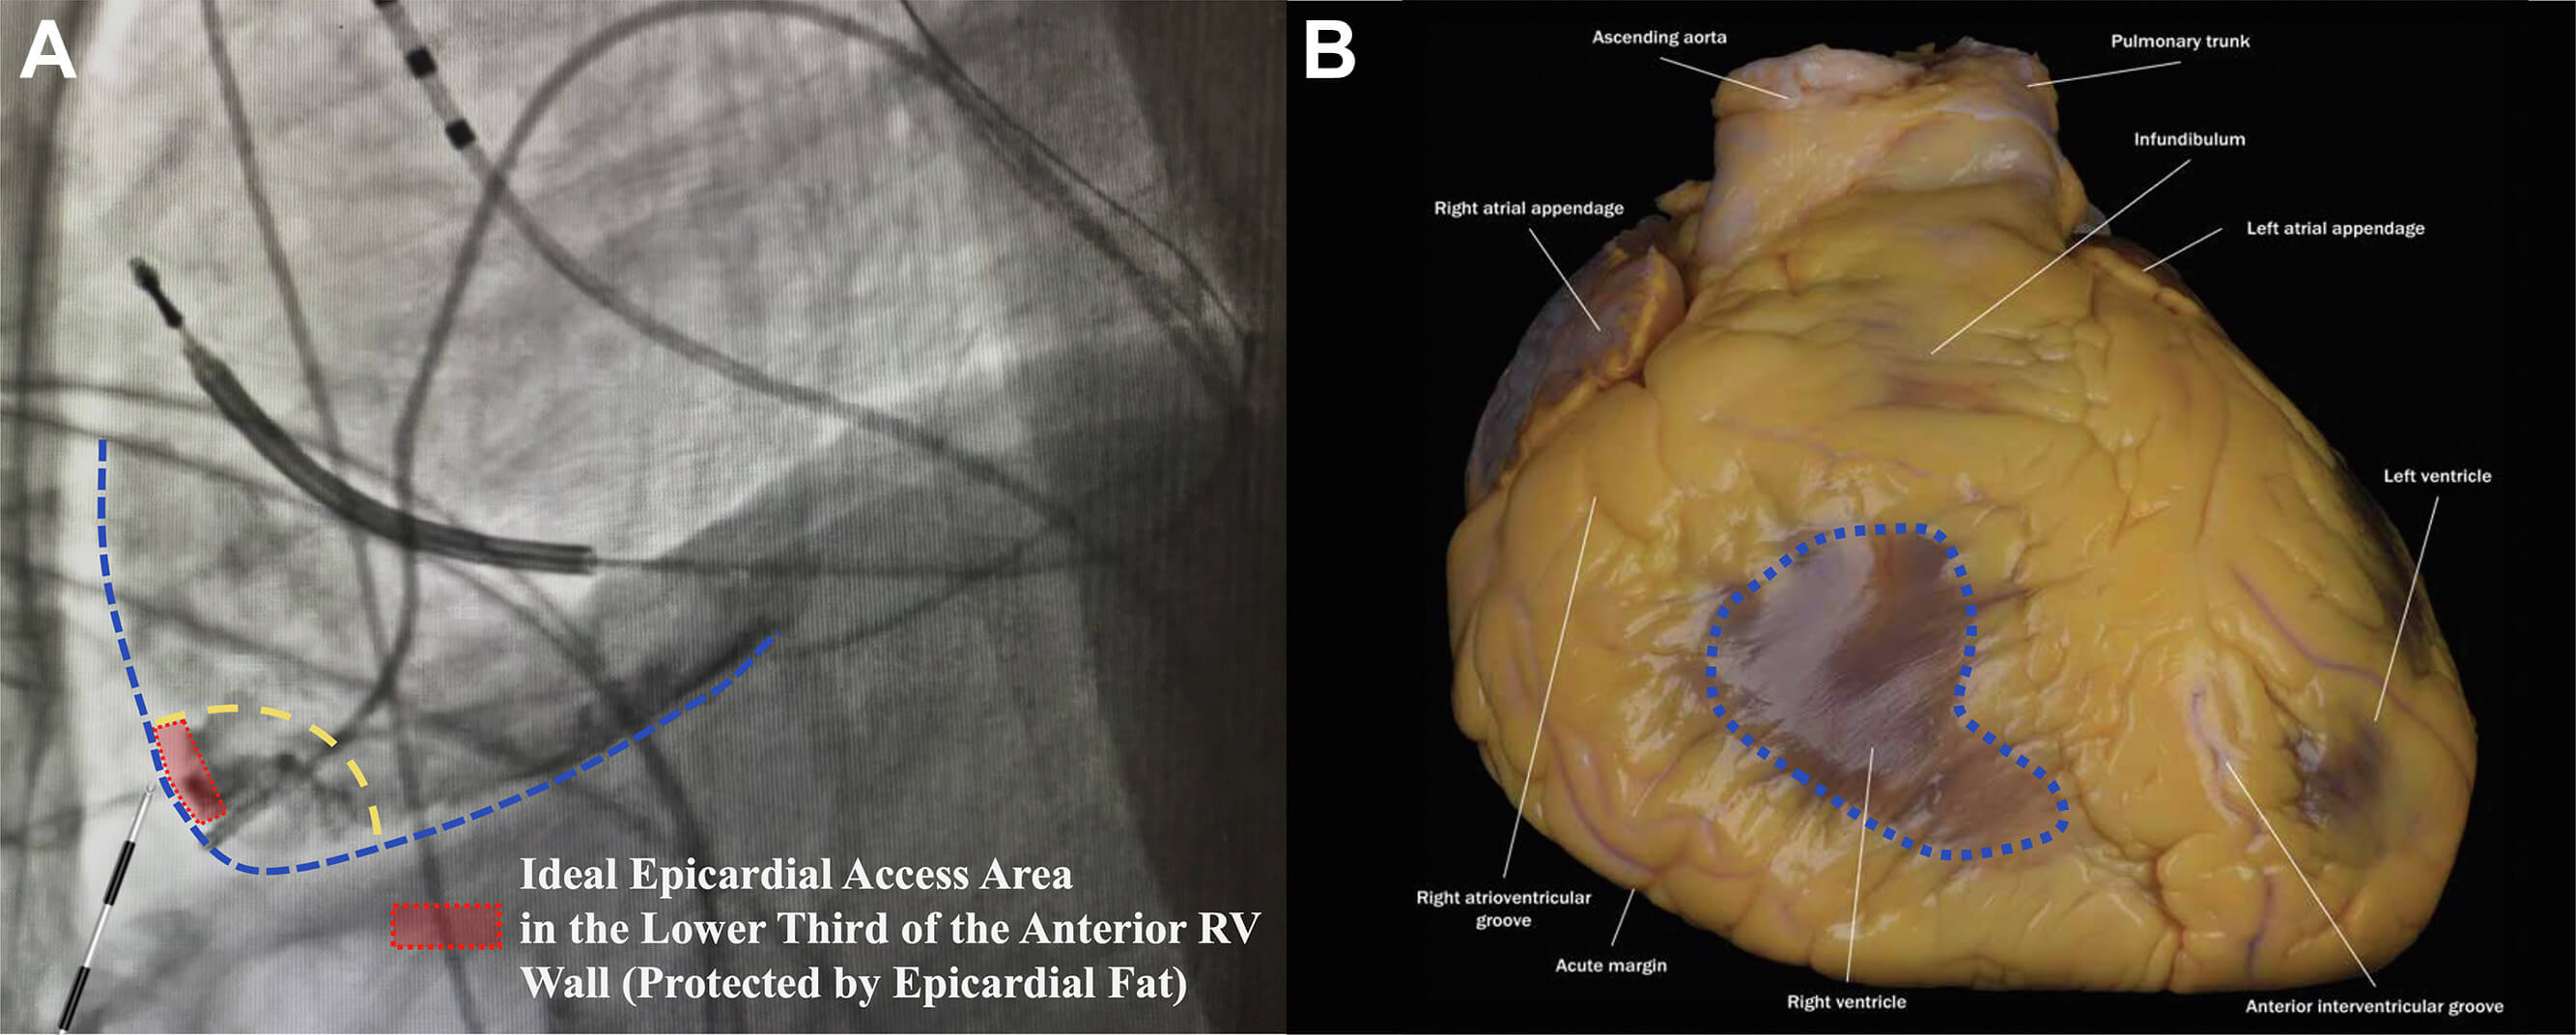

This technique was introduced by Romero et al. [16], who provided additional refinements to enhance the safety and reproducibility of the standard method. An important aspect of this approach is respiratory control with sustained end-expiratory apnea and RV angiography. RV angiography with a 5 Fr pigtail catheter was performed in both anteroposterior (AP) and left lateral (LL) fluoroscopic projections during apnea to minimize cardiac and diaphragmatic motion, which further delineated the RV border and guided the needle entry. Once the ideal needle trajectory was evaluated, a 17G Tuohy large-bore needle was advanced under LL projection while manually compressing the abdomen to flatten the needle trajectory and displace the intra-abdominal organs. The lower third of the RV anterior wall was targeted for the entry point with the anterior approach, where it is typically insulated by epicardial fat and is free from major coronary vessels. The other aspects of this technique are the same as the conventional approach. The SAFER technique emphasizes its wide availability by utilizing commonly available tools, although it remains unclear to what extent each step of the procedure, and in particular, RV angiography, adds value and safety to the access procedure compared to standard “dry” puncture while maintaining the patient in apnea. Fig. 5 (Ref. [16]) depicts the ideal epicardial puncture location (lower third of the anterior RV wall) with RV angiography.

Fig. 5.

Sustained apnea for epicardial access with right ventriculography (SAFER epicardial approach). (A) Delineation of the ideal pericardial puncture site in LL fluoroscopic projection at the lower third of the right ventricular (RV) wall (dotted red rectangle), leftward to the interventricular septum. This area is usually protected by epicardial fat in most patients. (B) Illustration of the area of the pericardium that should be avoided as it is not protected by epicardial fat (dotted blue area). This figure was modified from the original figure of Romero et al. [16].